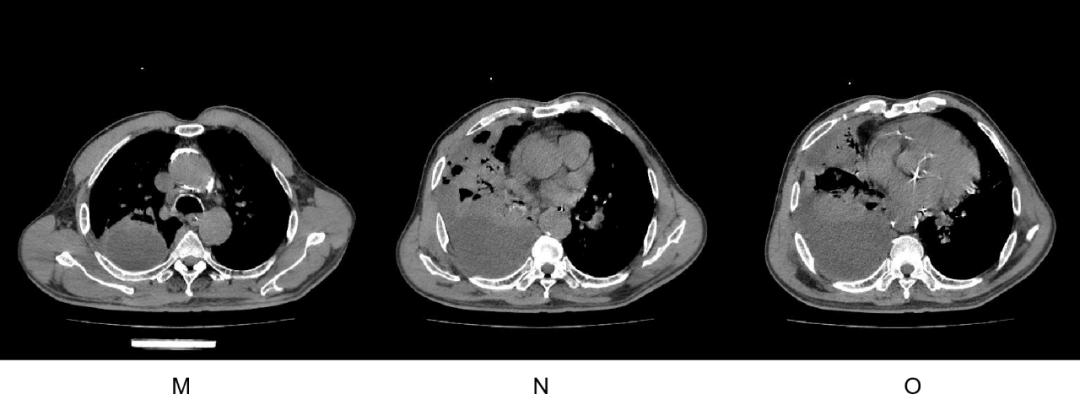

男,67 岁,右侧胸痛、腰痛 3 天,加重伴呼吸困难 1 天,入院后出现发热。

既往无糖尿病史,3 年前始吸烟酗酒。入院后血糖正常,2021-12-30 血常规:WBC 16.35 × 10^9/L,中性粒细胞 15.23 × 10^9/L,淋巴细胞 0.27 × 10^9/L,单核细胞 0.83 × 10^9/L,嗜酸性粒细胞 0 × 10^9/L,HGB 149 g/L,PLT 213 × 10^9/L。超敏 CRP 191.79 mg/L,PCT 9.11 ng/mL。

2022-1-2 起静点头孢哌酮舒巴坦 2 天无效,2022-1-4 复查胸 CT 加重,改用美罗培南治疗 2 天仍无效,2022-1-6 请本人会诊,因CT显示大的高张力液气平面空洞,且快速进展,考虑为星座链球菌 + 多种厌氧菌感染的肺脓肿脓胸,建议做胸腔积液 NGS,同时调整抗生素为大剂量青霉素 + 奥硝唑治疗,换药当天晚上开始不再发热,病情迅速好转。

2022-1-2 入院时

2022-1-4 进展时复查 CT

2022-1-14 治疗后

原高张力肺脓肿及脓胸间隔 2 天病灶迅速进展,出现液气平面,大剂量青霉素+奥硝唑治疗 8 天明显好转。

胸腔积液黄色浑浊,胸腔积液 NGS 结果回报: 星座链球菌 804 条 ,微小单胞菌 42040 条,解肝素拟杆菌 41287 条,口腔消化链球菌 22767 条,缓慢布雷德菌 12701 条,牙髓卟啉单胞菌 12701 条,麻疹孪生球菌 4254 条,侵肺戴阿李斯特菌 3456 条,具核梭杆菌 3020 条,中间普雷沃菌 1317 条,龈沟产线菌 769 条,齿垢密螺旋体 398 条,直肠弯曲菌 99 条。

【点评】

这一例是临床医生对星座链球菌肺脓肿脓胸的影像表现不熟悉,习惯性抗阴性菌治疗,星座链球菌往往与多种厌氧菌同时感染,脓腔张力很高,而星座链球菌生长需要厌氧环境及 5% 的 CO2,且单个病灶往往出现在下肺。星座链球菌感染应选择青霉素 + 咪硝唑类。